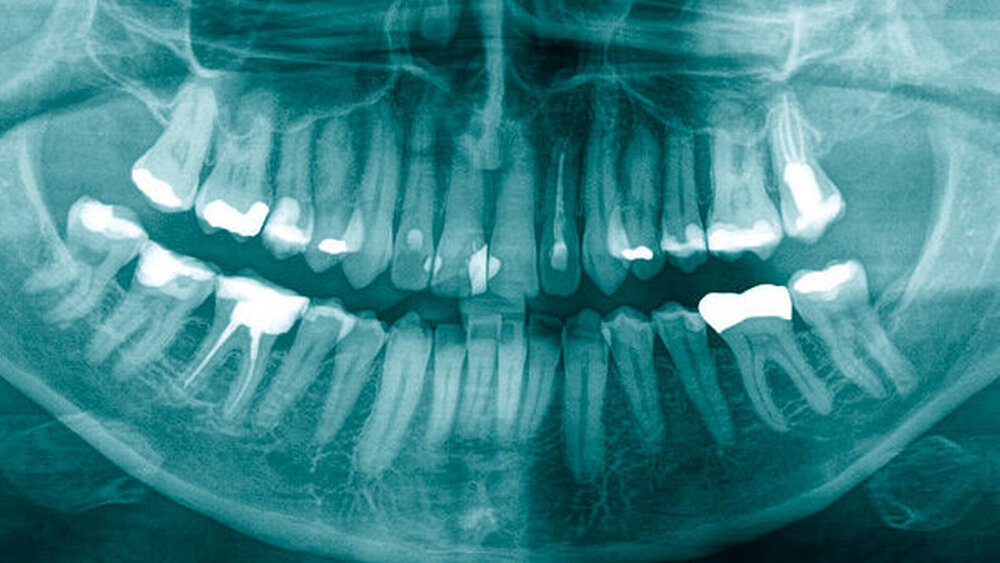

Klinisch waren die Zähne im zweiten Quadranten in einem regelrechten Zustand. Die Schleimhaut im Bereich des Oberkiefers linksseitig war reizfrei. Eine Fistel konnte nicht ausgemacht werden. Im Orthopantomogramm zeigte sich eine milchige Verschattung im Bereich der Kieferhöhle linksseitig (Abbildung 1). Es bestand der Verdacht auf eine nicht regelrecht knöchern konsolidierte Alveole regio 28. Die Nasenatmung linksseitig war im Vergleich gegenüber der rechten Seite leicht eingeschränkt.